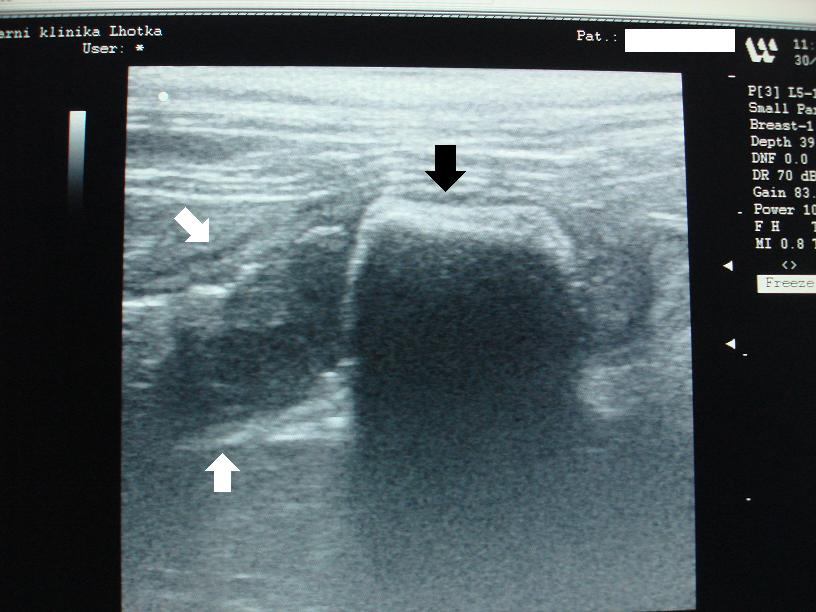

Na obrázku z ultrasonografu  ukazuje černá šipka na cizí těleso v tenkém střevě,  ze kterého je vidět jen jeho přivrácený  obrys.  Zbytek tělesa nám ultrasonografické vlny nepropouští, a  proto se za ním vytváří  černý sonografický  stín. Bílé šipky ukazují na rozšířené střevo před cizím tělesem, ve kterém stagnuje střevní obsah, kdežto za ním je střevo prázdné.

USG-CT-špunt do ucha